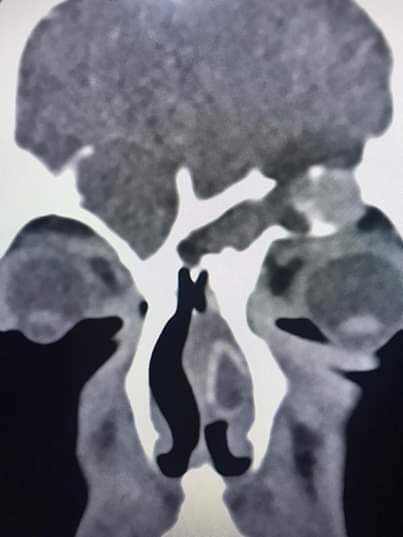

قام فريق طبي من دائرة الأذنية في الخدمات الطبية الملكية برئاسة العقيد الطبيب نبيل الشواقفة مستشار جراحة الأنف وقاع الجمجمة بإجراء عملية تنظير معقدة ونادرة لشاب يبلغ من العمر ٢٠ عاما، يعاني من التهاب فطري حاد ممتد إلى قاع الدماغ وحجرة العين مع وجود ثقب في قاع الجمجمة.

وبين الشواقفة ان المريض عندما راجع عيادة الأنف والأذن والحنجرة في مدينة الحسين الطبية كان يشكو من صداع شديد وانسداد في الأنف وصعوبة في التنفس، وبعد إجراء الفحص السريري والشعاعي تبين وجود إلتهاب حاد ممتد إلى قاع الجمجمة وحجرة العين وثقب في قاع الجمجمة، تقرر على أثرها إجراء العملية التي تعتبر من العمليات النادرة والمعقدة التي تحتاج فريق طبي متخصص .